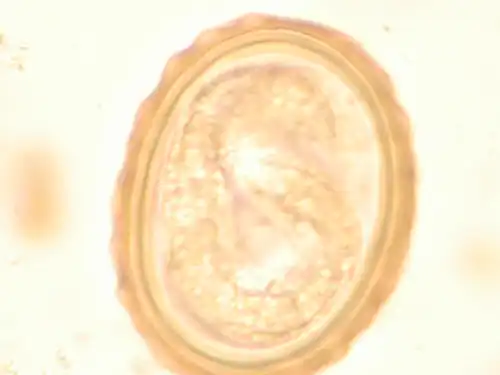

The larva of Ascaris lumbricoides developing in the egg -

Ascaris egg, incubation process: The Ascaris egg incubation process consists of placing the egg in a controlled environment, at 26 °C (79 °F) during 28 days, in acidic conditions. This process allows for the evaluation of an egg to determine if it is viable or not.

Most diagnoses are made by identifying the appearance of the worm or eggs in feces. Due to the large quantity of eggs laid, diagnosis can generally be made using only one or two fecal smears.[32] The diagnosis is usually incidental when the host passes a worm in the stool or vomit. The eggs can be seen in a smear of fresh feces examined on a glass slide under a microscope and there are various techniques to concentrate them first or increase their visibility, such as the ether sedimentation method or the Kato technique. The eggs have a characteristic shape: they are oval with a thick, mamillated shell (covered with rounded mounds or lumps), measuring 35–50 micrometer in diameter and 40–70 in length. During pulmonary disease, larvae may be found in fluids aspirated from the lungs. White blood cell counts may demonstrate peripheral eosinophilia; this is common in many parasitic infections and is not specific to ascariasis. On X-ray, 15–35 cm long filling defects, sometimes with a whirled appearance (bolus of worms).